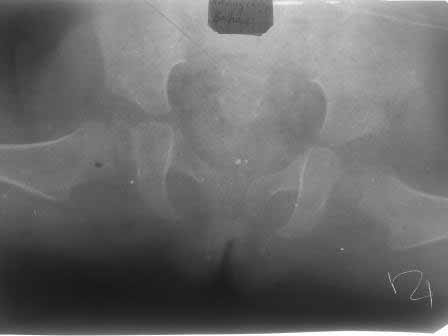

через 9 месяцев после вправления